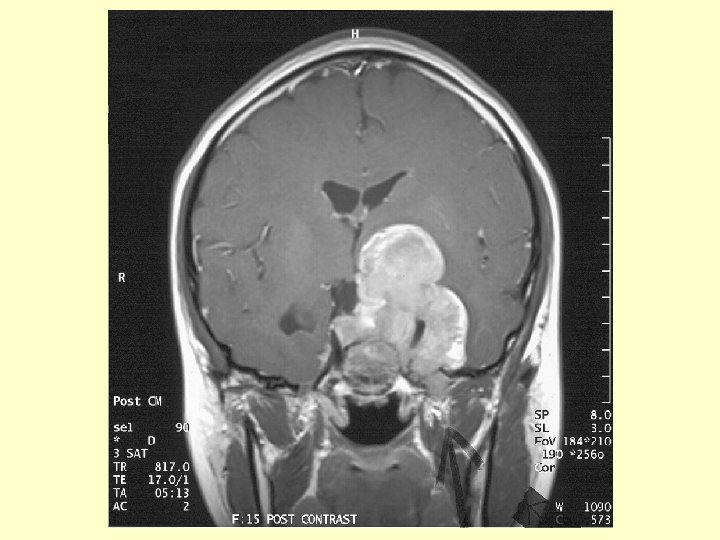

Investigation (3) • CT scan brain: A large hyperdense mass at the left parasellar region. It measured 4. 6 x 4. 4 cm. No calcification or cystic component found. It was extra-axial in location & extended into the pituitary fossa, middle & posterior cranial fossae. The left carotid artery was encased. The optic chiasm was compressed. There was mild hydrocephalus noted due to compression at level of Foramen of Monro.

Investigation (4) • MRI brain: A contrast enhanced solid tumor , measuring 4. 6 x 4. 8 x 6. 3 cm , was occupying whole sella with superior & inferior extension. Superiorly it extended to suprasellar cistern compressing left hypothalamus with the left cerebral peduncle being compressed & elevated. The frontal horn of left lateral ventricle was compressed from below. The left carotid artery was encased by tumor. The optic chiasm could not be identified but was likely to be compressed & encased.

Investigation (5) • MRI brain ( cont’d) Laterally the mass was compressing left temporal lobe & was occupying cavernous sinuses & Meckel’s cave. The mass also occupied right cavernous sinus & encasing right carotid artery. Inferiorly, the mass eroded through sellar floor & occupied sphenoid sinus with floor of sphenoid sinus preserved. Posteriorly the mass extended into left cerebellopontine angle cistern and caused compression of left of pons. Fourth ventricle not distorted.